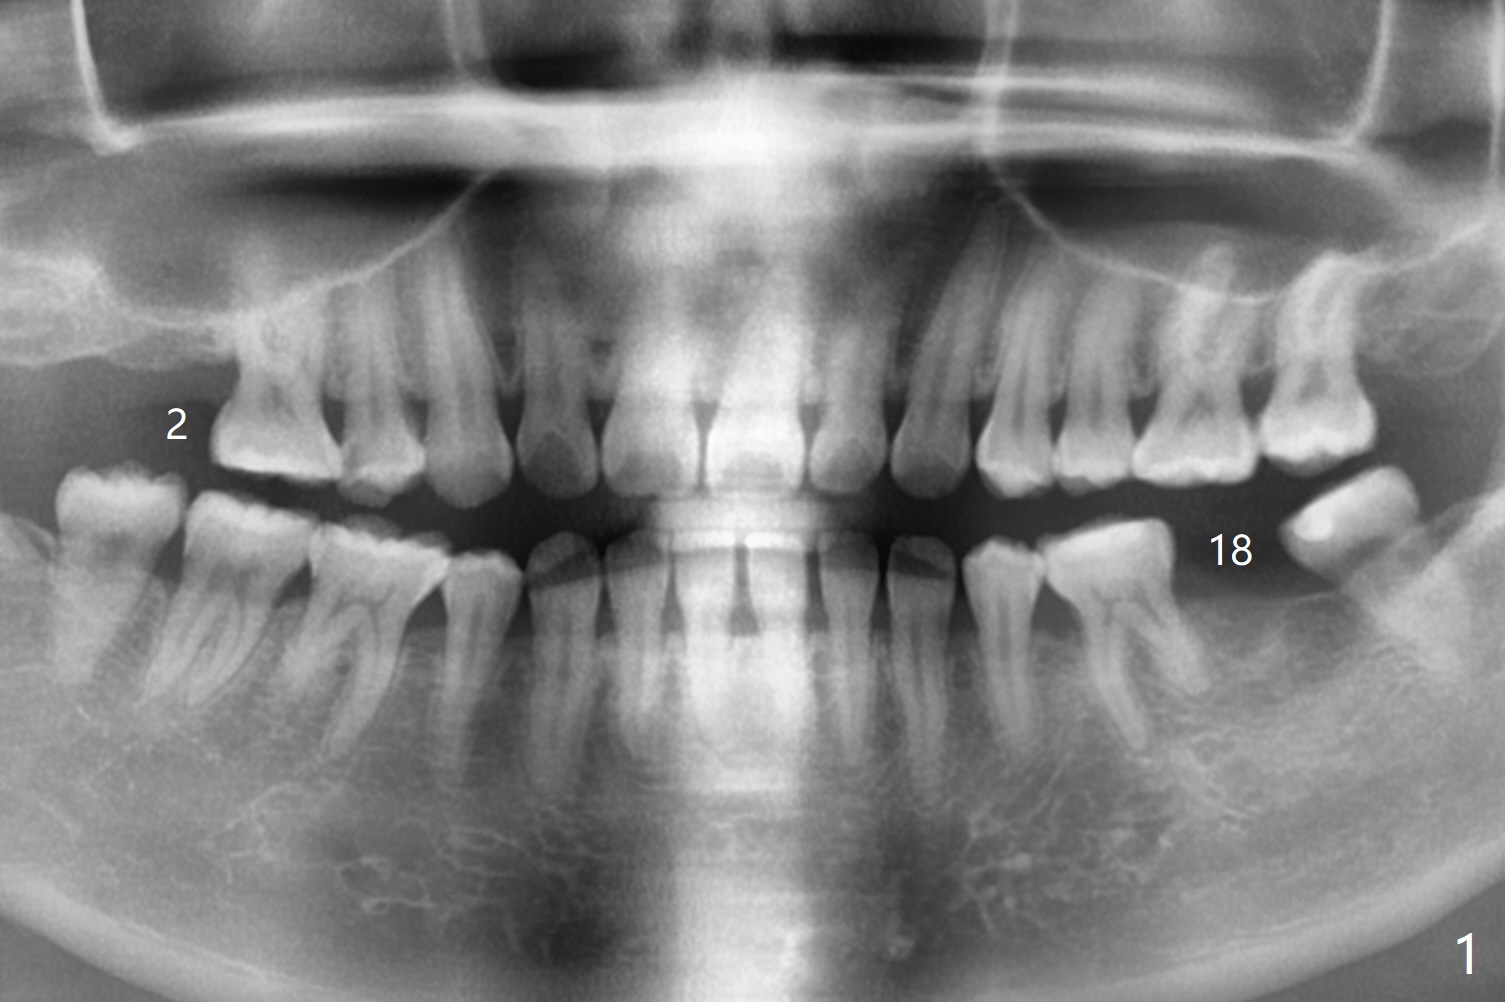

A 25-year-old woman had #2 and 18 extracted ~ 1 year ago (Fig.1). Because of the short and loose bone at #2, a short implant will be placed with sinus lift (PRF, Fig.2). If needed, probe mesiobuccal aspect of the osteotomy when it is close to the sinus floor to detect early sinus floor perforation before water lifting. It would be safer to use water lifting after the 1st sinus safe drill is used. Then water lifting and the 2nd sinus safe drill, et al. To reduce micromovement, a healing screw will be most likely placed instead of a healing abutment. In contrast, a healing abutment is possible at #18 (Fig.3).

Return to Upper Lower Molar Immediate Implant, Trajectory II Xin Wei, DDS, PhD, MS 1st edition 09/21/2019, last revision 02/02/2020